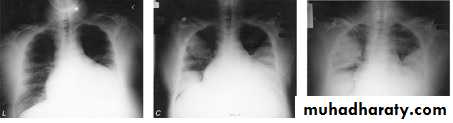

Severe acute respiratory distress syndrome (SARS)

Corona virus, is an RNA virusSARS rose to prominence in late 2002 in China. followed by an international outbreak

high fever (> 38°C), malaise and muscle aches and later a dry cough with shortness of breath or difficulty in breathing, with history close contact within 10 days of onset of symptoms with a person known to be a suspect SARS case is typical.

The chest X-ray is usually indicative of pneumonia.

Chest x-rays of a 46-year-old man with SARS. The left lower lung infiltrate seen initially (A) progressed to multiple bilateral opacities (B).